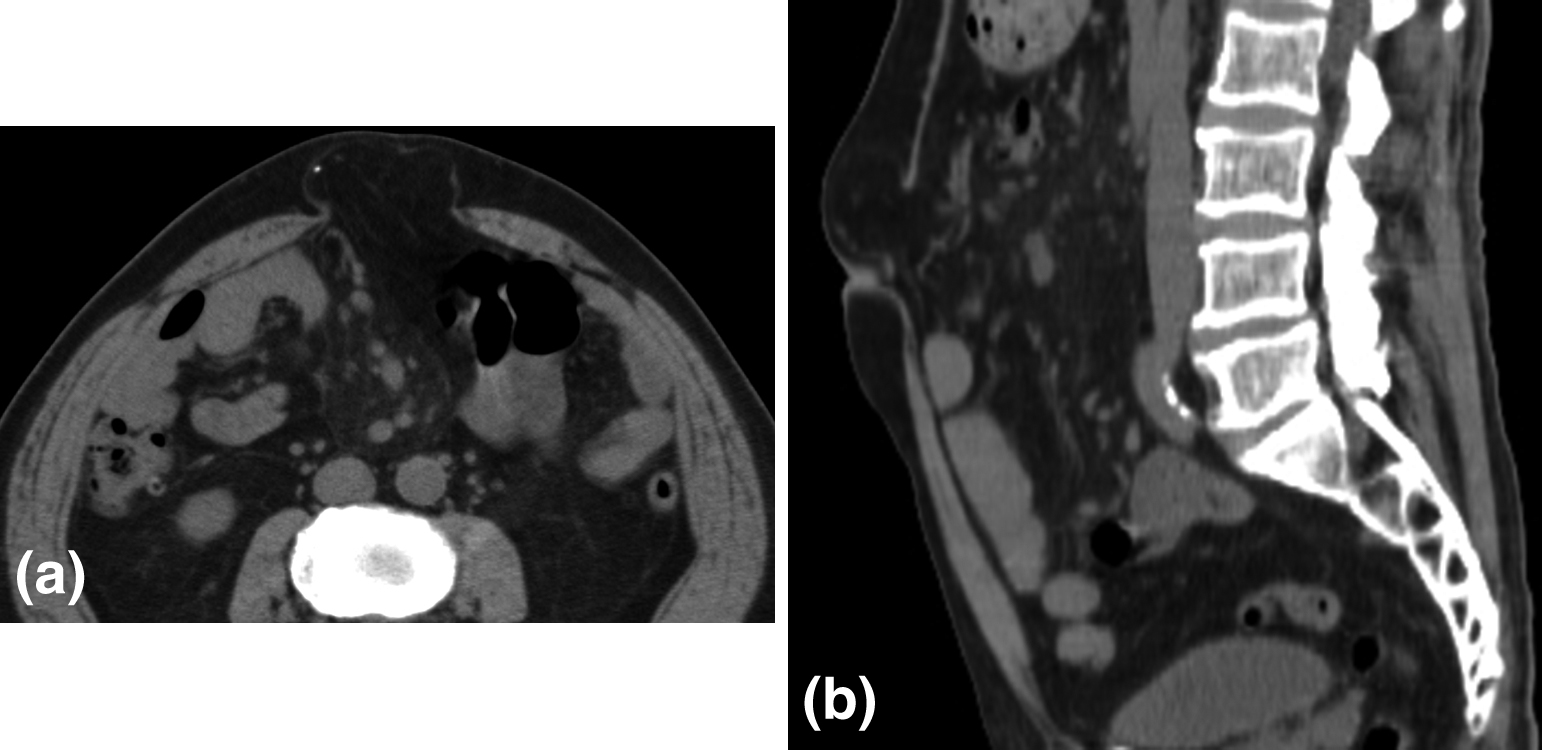

腹部単純CT所見:臍上部に51×47 mmのヘルニア門を有する腹壁瘢痕ヘルニアを認めた(Fig. 2).膵癌の転移再発所見は認めなかった.

Abdominal CT showed an incisional hernia, 51 mm×47 mm in size at the cranial side of the navel. (a) axial image. (b) sagittal image.